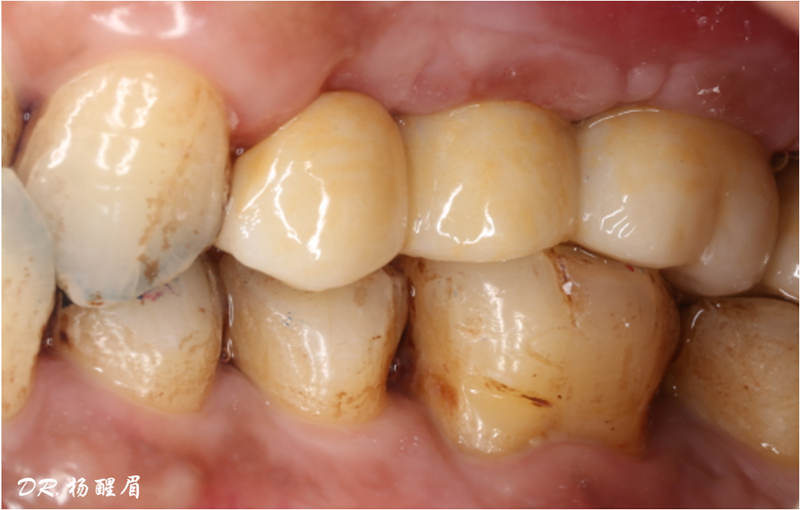

修復完成

®多顆植體位點及角度的精確性,確保后期修復方案順利完成,也使患者能在使用過程中承受最佳的咬合力

®完成3顆植體的植入,植體位點如術前方案設計,均在同軸線。